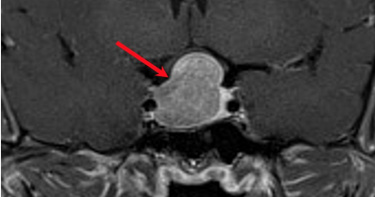

50歲的上班族陳先生,這2年來容貌外觀產生不小的變化,一開始額頭及下巴變得愈來愈突出,接著鼻子與手也變大了,身高沒有改變,但鞋子愈穿愈緊、愈換愈大,就醫診斷發現罹患肢端肥大症,經醫師評估接受腦部微創手術後才得以改善。肢端肥大症是一種少見的疾病,常因腦下垂體腫瘤不正常分泌生長激素所導致,患者除了外觀上產生很明顯的改變外,也會有多汗多油、皮膚變粗及性功能障礙等問題,雖然是一種漸行性的疾病,但因臟器也會隨著內分泌的不正常而增生膨大,若沒有即時發現並治療,平均壽命約減少5-10年。陳先生經由內分泌暨新陳代謝科診斷為肢端肥大症後,核磁共振影像進一步定位長在腦下垂體的腫瘤,馬偕紀念醫院神經外科主治醫師詹雲凱表示,以往類似陳先生這樣必須接受腦部手術的病人,必須先在頭部劃下一道長長的手術傷口,並取下大範圍的頭骨後,才能進行腦部腫瘤的手術切除。現在透過腦瘤微創手術以及經鼻內視鏡顱底手術的精進,陳先生可以免於在手術室裡接受傳統大型的開顱手術,詹雲凱表示,腦瘤微創手術必須具備「最大範圍切除」與「最小程度破壞」兩大特點,手術過程中,需具備清晰之內視鏡影像系統,搭配精良的術中導航系統,以利準確定位腫瘤及提供即時新的影像。馬偕紀念醫院內分泌暨新陳代謝科主治醫師黃俊達表示,陳先生接受神經外科腦下垂體腫瘤「連根拔除」手術後,大手大腳與外觀變化的情況已逐漸改善,目前仍持續在門診追蹤。臨床上,肢端肥大症年發生率約為每百萬人約2-11人,手術的治癒率與腦下垂體腫瘤大小及外科醫師的經驗有關,針對小於1公分的腫瘤,手術治癒率可高達75%,但如果已經侵犯到周邊組織的較大腫瘤,手術治癒率則降至30-50%,無法透過手術解決問題時,則必須仰賴長時間的藥物治療。黃俊達指出,肢端肥大症者已膨大的臟器是「回不去了」,確診後的第一要務就在為臟器膨大設定停損點,在治療時會特別注意受到影響的臟器功能性,由於此類病人易有較高罹患高血壓、糖尿病、心臟肥大及因舌頭肥大導致睡眠呼吸中止症的風險,因此規則追蹤返診,處理因生長激素過多導致的共病現象是十分重要的。

肢端肥大症難揪出 恐短命5到10年

50歲的陳先生最近二年來容貌外觀產生不小的變化,一開始額頭及下巴變得突出,鼻子與手也變大,儘管身高沒有改變,但鞋子越穿越緊、越換越大雙,就醫發現罹患「肢端肥大症」。醫師指出,肢端肥大症是因為腦下垂體腫瘤分泌過多的生長激素,如果沒有及時治療,臟器增生膨大而影響功能,平均壽命恐減少5到10年。馬偕紀念醫院內分泌暨新陳代謝科主治醫師黃俊達說明,肢端肥大症是一種少見疾病,發生率大約每百萬人有2到11人,原因是腦下垂體腫瘤分泌過多的生長激素;由於病程進展速度慢,患者不易發現,病人手腳會逐漸變大、額頭突起、鼻子變大,也會有多汗多油、皮膚變粗及性功能障礙等問題。不僅如此,由於臟器會隨著內分泌異常而增生膨大,若沒有及時發現並治療,平均壽命約減少5到10年。黃俊達指出「膨大的臟器是回不去了」,因此第一要務是設定停損點,避免臟器繼續膨大;由於肢端肥大症患者易罹患高血壓、糖尿病、心臟肥大,因舌頭肥大也容易導致睡眠呼吸中止症,因此規律追蹤回診是十分重要的。陳先生經診斷為肢端肥大症後,接受核磁共振影像檢查,進一步定位腦下垂體腫瘤。馬偕紀念醫院神經外科主治醫師詹雲凱表示,過去像陳先生這樣需要腦部手術的病人,要在頭部劃下一道長長的手術傷口,取下大範圍的頭骨後才能切除腦部腫瘤,現在透過腦瘤微創手術以及經鼻內視鏡顱底手術,具備「最大範圍切除」與「最小程度破壞」兩大特點,可免於開顱手術。黃俊達表示,陳先生接受手術後,大手大腳與外觀變化情況已逐漸改善,目前仍持續在門診追蹤。一般而言,肢端肥大症患者多半由內科醫師發現,並需要整合外科醫師進行手術治療,接著再由內科醫師追蹤與長期觀察,因此醫療團隊的組成陣容也格外堅強。詹雲凱提醒,由於每位病人腦瘤位置與大小均不相同,也並非所有病人都適合使用微創手術來切除腦瘤,解決腦部腫瘤的問題需要明確的診斷與充分的檢查,再搭配良好的精良的外科手術,才能解決病灶。